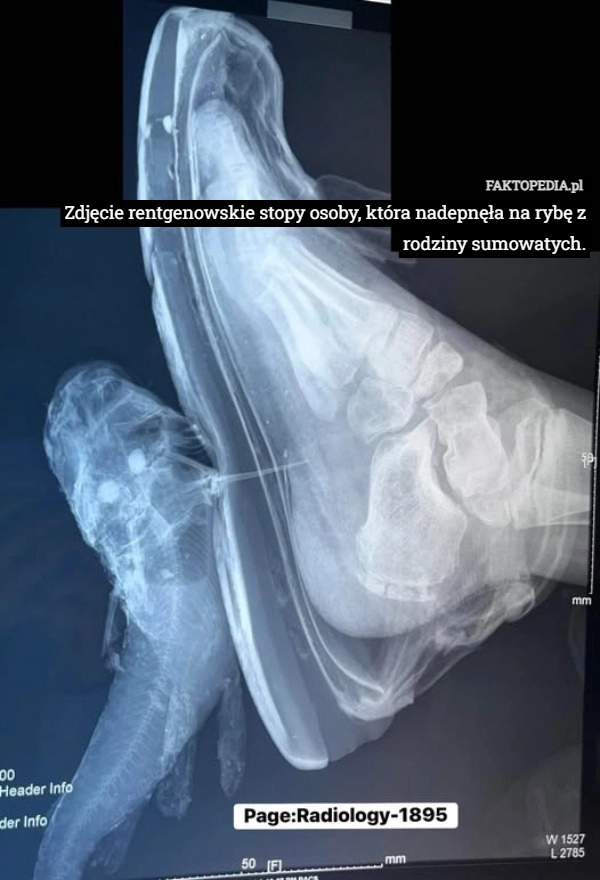

Zdjęcie rentgenowskie stopy osoby, która nadepnęła na rybę z rodziny sumowatych.